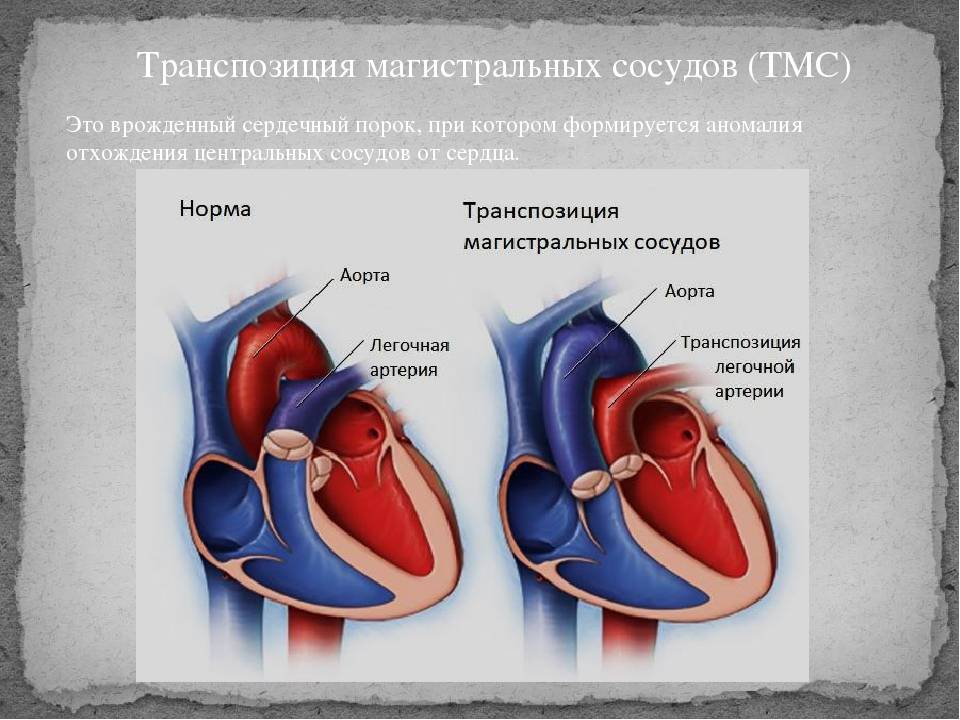

Пороки сердечно-сосудистой системы: виды и признаки